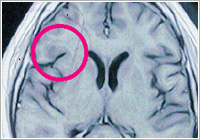

ë³‘ì› ê²€ì§„ ê²°ê³¼ ì´ì „ì˜ MRI 사진ì—는 다발성 뇌경화ì¦ì˜ ì „í˜•ì ì¸ í™œë™ì„±ì˜ ì—¼ì¦ ì†Œê²¬ì´ ìžˆì—ˆìœ¼ë‚˜ 성회 í›„ì˜ MRI 사진ì—는 ê·¸ë ‡ê²Œ 활ë™ì 으로 ë³´ì˜€ë˜ ë‡Œ ì—¼ì¦ ì†Œê²¬ì€ ëšœë ·ì´ ì‚¬ë¼ì ¸ 회복ë˜ëŠ” ì†Œê²¬ì„ ë³´ì—¬ 주었습니다.

기ë„받기 1ë…„ ì „ì˜ MRI (í˜„ì €í•œ ì—¼ì¦ ì†Œê²¬ì„ ë³´ì´ê³ 있ìŒ)

기ë„ë°›ì€ ì§í›„ì˜ MRI (기존 ì—¼ì¦ ì†Œê²¬ì´ ë³´ì´ì§€ 않ìŒ)